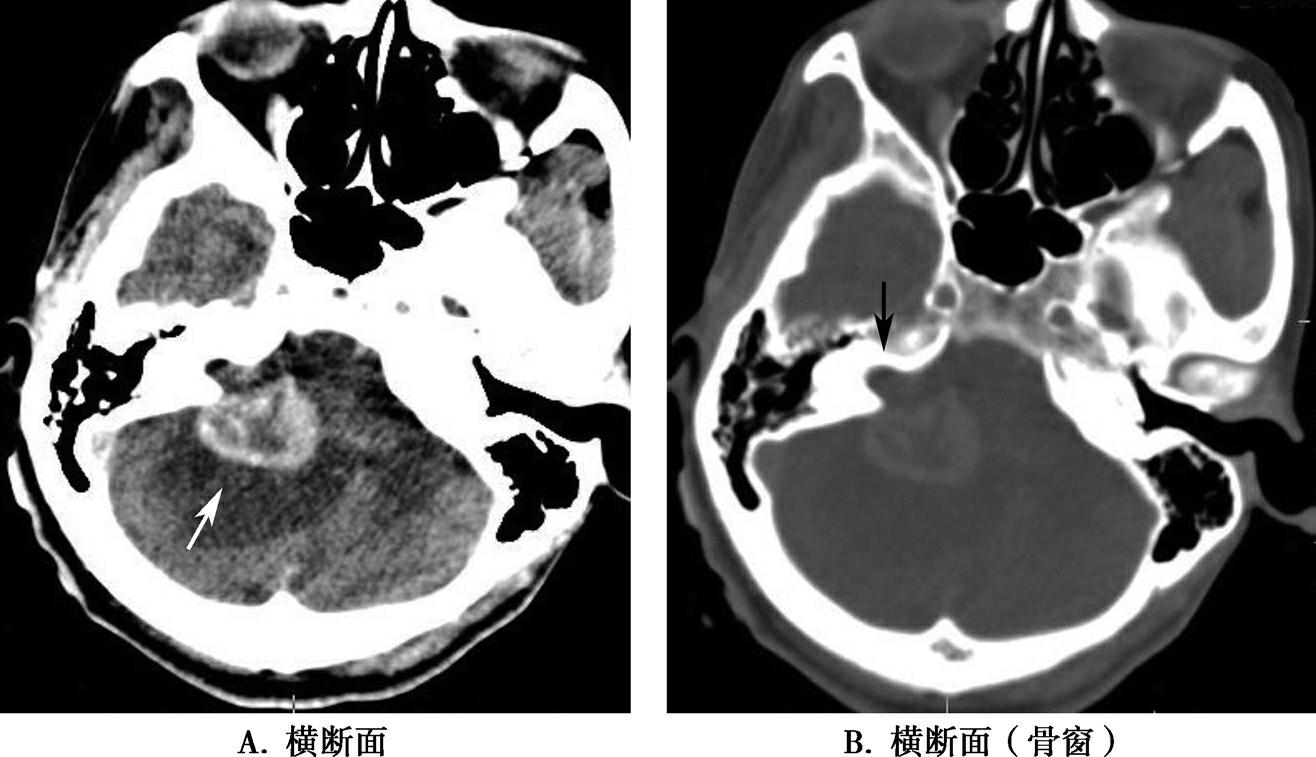

破裂孔、卵圆孔、棘孔及斜坡等均为重要的解剖结构,临床常见疾病如鼻咽癌常侵犯上述结构(图1-2-3)。颈静脉孔区较常见的肿瘤为颈静脉球瘤,常伴有颈静脉孔及其邻近骨质的破坏(图1-2-4)。

图1-2-3 鼻咽癌颅底骨质破坏

A.横断面;B.横断面(骨窗)

骨窗示左侧岩尖、斜坡、左侧蝶骨大翼骨质破坏、受侵(白箭),肿瘤经破裂孔侵入颅内(黑箭头)